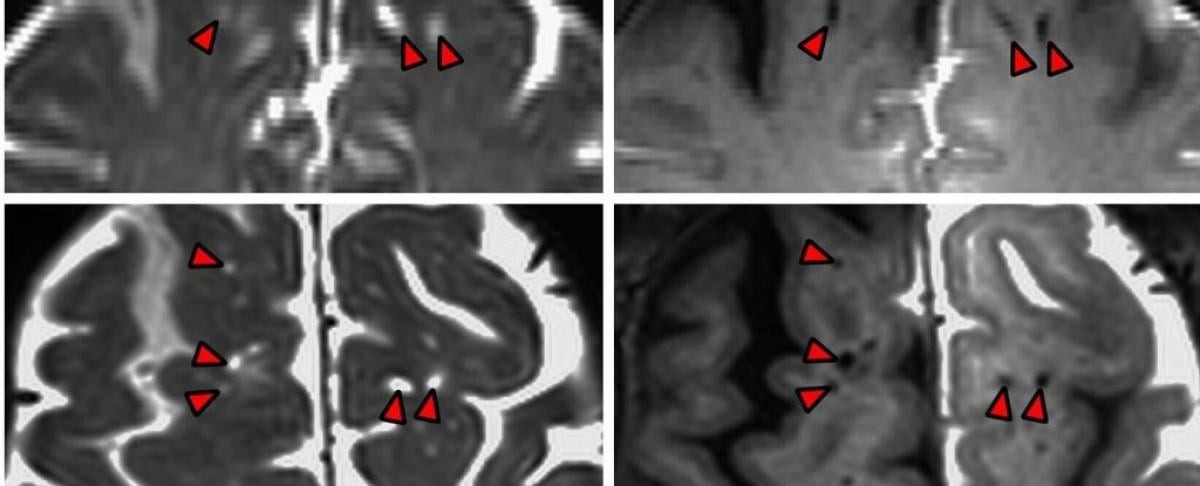

Neurochirurgė Erin Yamamoto pažymėjo, kad jų atlikto tyrimo magnetinio rezonanso nuotraukose „iš tikrųjų matyti, kaip tamsios perivaskulinės smegenų erdvės laikui bėgant tampa šviesios“, nes kontrastinis indikatorius prasiskverbia giliau.

Šie smegenų skysčio kanalai žmogaus smegenyse buvo vizualizuoti ir anksčiau, tačiau kadangi tyrėjai atliko MRT tyrimus praėjus 12, 24 ir 48 valandoms po operacijos, jie galėjo geriau stebėti skysčio dinamiką.

Rezultatai rodo, kad smegenų skysčio kanalai nėra sustingusios, skysčio pripildytos struktūros, o „funkciniai kanalai“, kurie palengvina „smegenų skysčio pasiskirstymą smegenyse“.